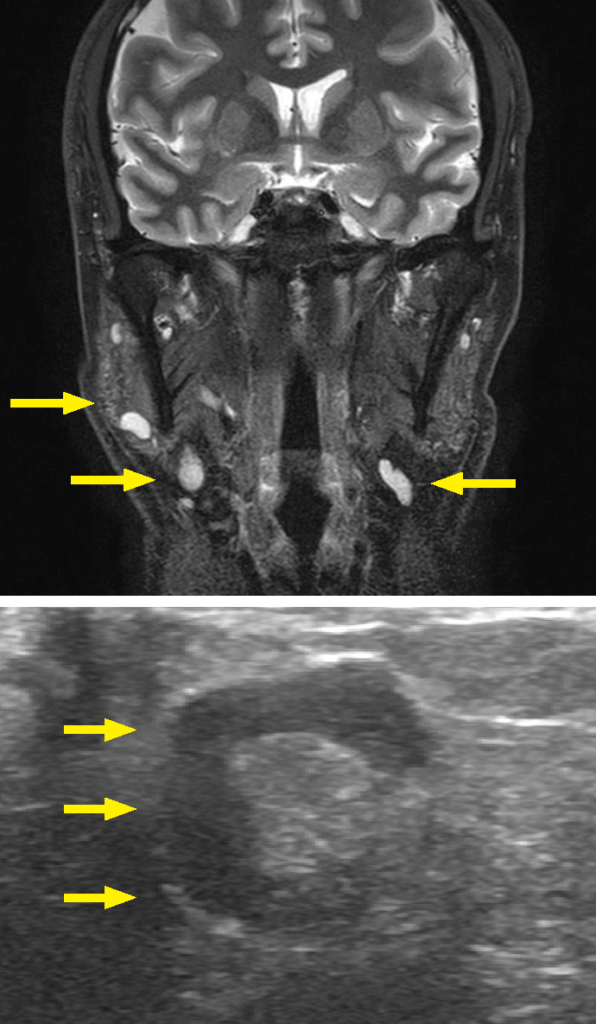

画像所見;MRI所見では、両側頸部リンパ節が複数腫脹している。超音波画像所見では著明な腫大を認めるが、門部構造は保たれている。